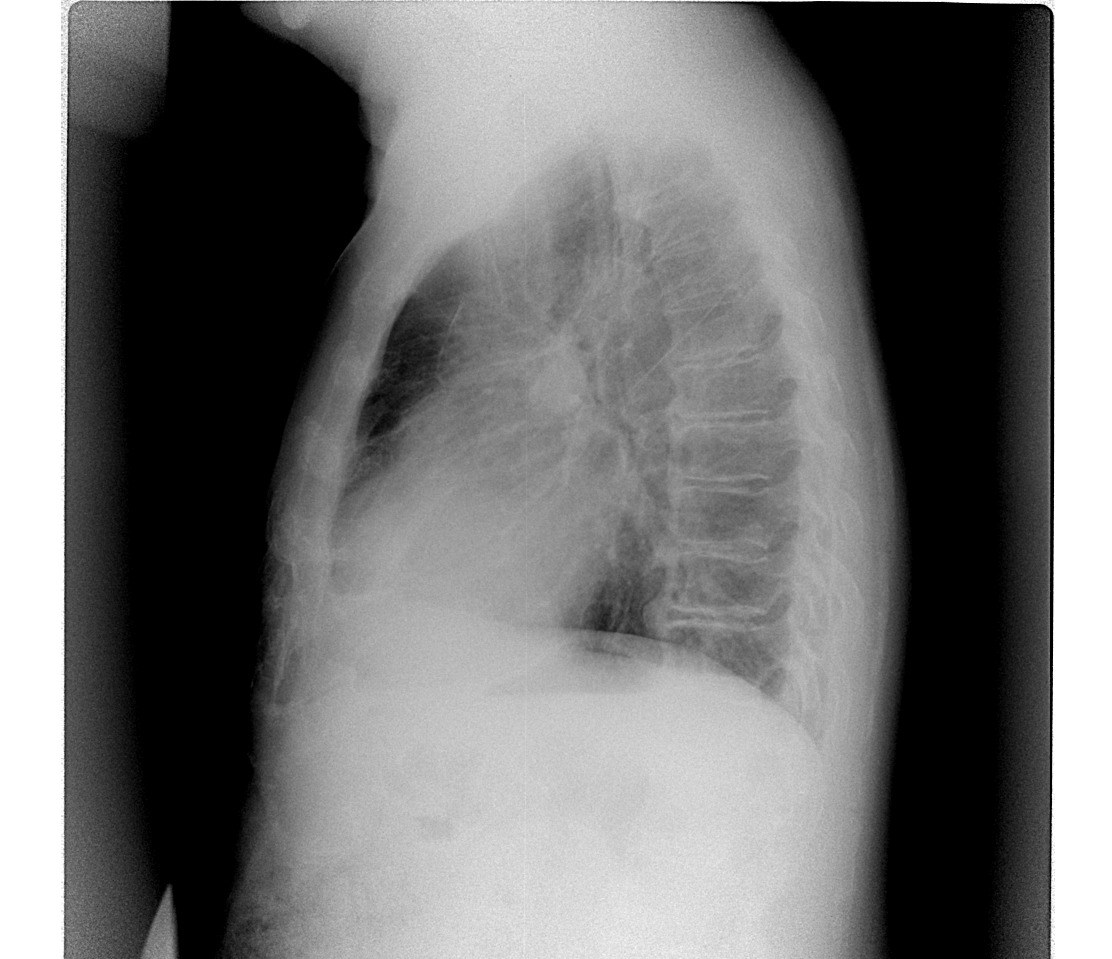

Шварта. Видно на боковом.

Эти так называемые дела можно назвать уплотнённой междолевой плеврой.)) Это главная которая. У кардиологических, бывает, плотнеет она.